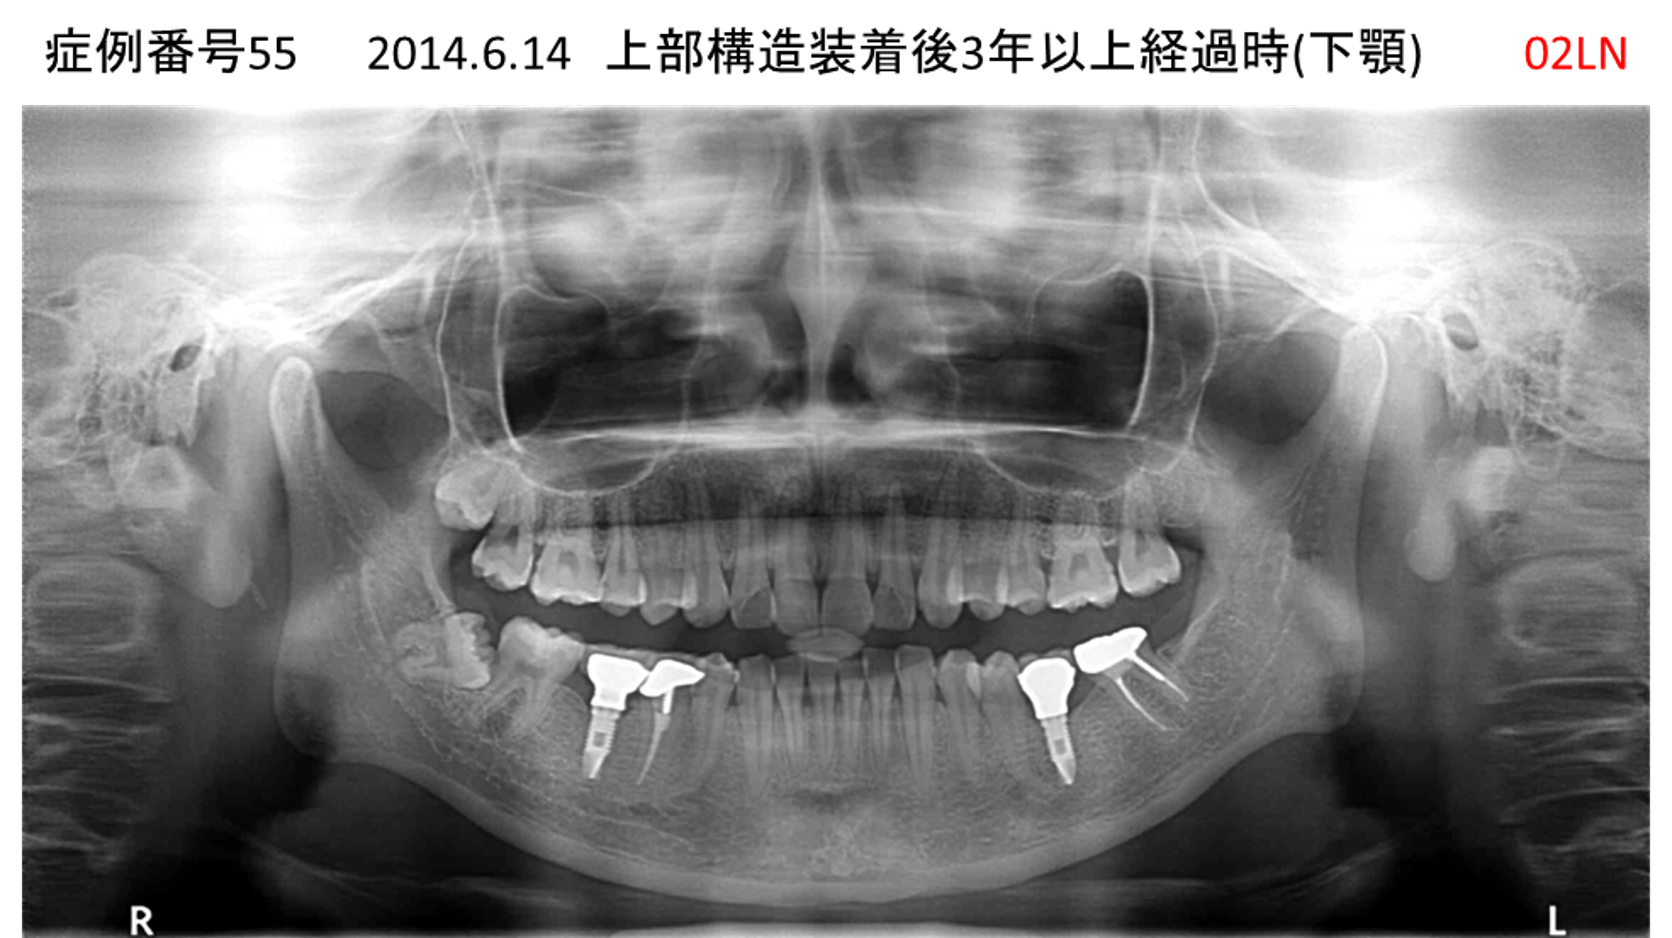

奥歯で噛めない患者様のインプラント症例

| 治療名称 |

インプラント |

| 治療費用 |

365万円+税 |

| 治療期間 |

5か月 |

| 患者さんの症状(主訴) |

奥歯で噛めない。上の前歯が揺れてきた。 |

| 治療内容 |

抜歯即時インプラント |

| 治療結果 |

食事に困らない。見た目がとても良くなった。 |

| 治療の注意点(リスク/副作用) |

インプラントが壊れたら再治療が必要 |